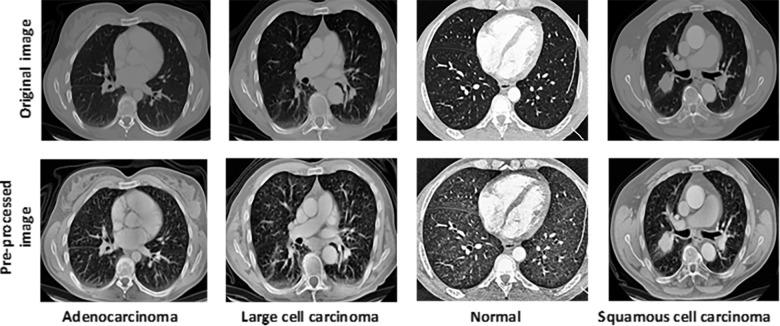

Lung cancer (LC) is a leading cause of cancer-related fatalities worldwide, underscoring the urgency of early detection for improved patient outcomes. The main objective of this research is to harness the noble strategies of artificial intelligence for identifying and classifying lung cancers more precisely from CT scan images at the early stage. This study introduces a novel lung cancer detection method, which was mainly focused on Convolutional Neural Networks (CNN) and was later customized for binary and multiclass classification utilizing a publicly available dataset of chest CT scan images of lung cancer. The main contribution of this research lies in its use of a hybrid CNN-SVD (Singular Value Decomposition) method and the use of a robust voting ensemble approach, which results in superior accuracy and effectiveness for mitigating potential errors. By employing contrast-limited adaptive histogram equalization (CLAHE), contrast-enhanced images were generated with minimal noise and prominent distinctive features. Subsequently, a CNN-SVD-Ensemble model was implemented to extract important features and reduce dimensionality. The extracted features were then processed by a set of ML algorithms along with a voting ensemble approach. Additionally, Gradient-weighted Class Activation Mapping (Grad-CAM) was integrated as an explainable AI (XAI) technique for enhancing model transparency by highlighting key influencing regions in the CT scans, which improved interpretability and ensured reliable and trustworthy results for clinical applications. This research offered state-of-the-art results, which achieved remarkable performance metrics with an accuracy, AUC, precision, recall, F1 score, Cohen's Kappa and Matthews Correlation Coefficient (MCC) of 99.49%, 99.73%, 100%, 99%, 99%, 99.15% and 99.16%, respectively, addressing the prior research gaps and setting a new benchmark in the field. Furthermore, in binary class classification, all the performance indicators attained a perfect score of 100%. The robustness of the suggested approach offered more reliable and impactful insights in the medical field, thus improving existing knowledge and setting the stage for future innovations.

肺癌是全球癌症相关死亡的主要原因,这凸显了早期检测以改善患者预后的紧迫性。本研究的主要目的是利用人工智能的先进策略,在早期从CT扫描图像中更精确地识别和分类肺癌。本研究介绍了一种新颖的肺癌检测方法,该方法主要聚焦于卷积神经网络(CNN),随后利用公开可用的肺癌胸部CT扫描图像数据集针对二分类和多分类进行了定制。本研究的主要贡献在于使用了混合CNN-奇异值分解(SVD)方法以及稳健的投票集成方法,这在减轻潜在误差方面具有卓越的准确性和有效性。通过采用对比度受限自适应直方图均衡化(CLAHE),生成了噪声最小且具有突出显著特征的对比度增强图像。随后,实施了CNN-SVD-集成模型以提取重要特征并降低维度。然后,提取的特征通过一组机器学习算法以及投票集成方法进行处理。此外,梯度加权类激活映射(Grad-CAM)作为一种可解释人工智能(XAI)技术被集成进来,通过突出CT扫描中的关键影响区域来提高模型透明度,这提高了可解释性并确保了临床应用结果的可靠和可信。本研究提供了前沿成果,在准确率、AUC、精确率、召回率、F1分数、科恩卡帕系数和马修斯相关系数(MCC)方面分别达到了99.49%、99.73%、100%、99%、99%、99.15%和99.16%的卓越性能指标,弥补了先前的研究空白并在该领域树立了新的标杆。此外,在二分类中,所有性能指标均获得了满分100%。所提出方法的稳健性在医学领域提供了更可靠且有影响力的见解,从而增进了现有知识并为未来创新奠定了基础。